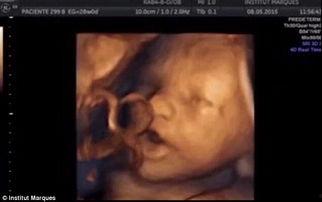

视频中,我们可以看到宝宝的小手和小脚在妈妈肚子里挥舞,仿佛在向世界打招呼。他们的眼睛虽然还紧闭着,但已经能够感受到外界的光线。这个时期的宝宝,已经能够听到妈妈的声音,甚至能够感受到妈妈的情绪。

1. 身体发育:在26周时,宝宝的身长大约在30-35厘米,体重在600-700克左右。他们的身体比例逐渐协调,头部相对于身体来说,已经不再那么大了。